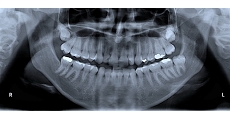

現在のお口の中の状態を調べます。

レントゲンをはじめ、細菌検査や歯周組織検査(歯周病の進行具合を調べる検査)を行います。